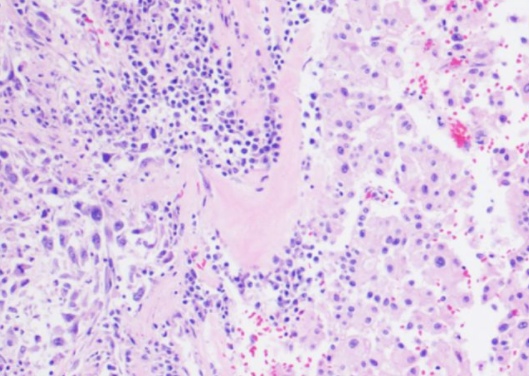

肾嫌色细胞癌是一种非常见的肾细胞恶性肿瘤,但与普通的肾细胞恶性肿瘤相比,它的恶性程度相对较低,它的形态比较特殊,恶性程度不高,根据临床医学认识,它起源于肾集合管上皮,目前在治疗此类恶性肿瘤时,大多会进行根治性切除。

全肾脏切除后往往预后效果好,与同期其他类型的恶性肿瘤相比,它的5年生存期比例相对较大。

对于患者来说,做到早发现早治疗相当重要。它的早期症状相对较少,但是肿瘤增大后可以出现明显的血尿、持续性腰痛,同时多伴有腹部包块,以上症状也被临床医学上称之为肾癌的三联征,若出现以上症状要引起重视。